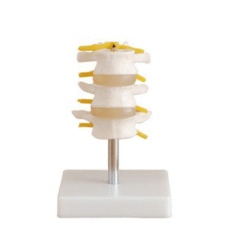

Skeleton Models(human bone, muscle, etc.)